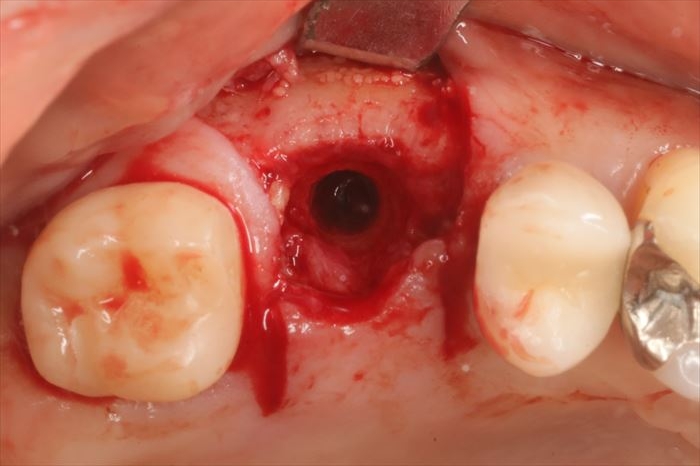

ここからはフィクスチャーリムーバーキットを用いて逆回転させ撤去していきます。

インプラントを撤去したあとは金属切削片がわずかに残っていますので掻爬(そうは)して取り除きます。

粘膜を剥離して骨の状態を確認します。

CTデータ通り、すり鉢状に骨吸収が起こっています。

ここから適切な位置にドリリングしなおします。